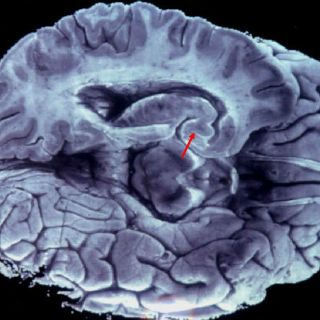

CIUDAD DE MÉXICO (19/JUL/2015).- La Secretaría de Ciencia, Tecnología e Innovación busca hackear el cerebro humano a través de impulsos electromagnéticos para disminuir padecimientos como el dolor crónico, ayudar en la recuperación del habla en pacientes con infartos cerebrales y reducir los efectos del Parkinson.

En cuanto a su funcionamiento, Carlos David Castillo, especialista en neurología y neurofisiología, explicó que no se trata de imanes ni chacras como muchos dicen, sino de generar campos magnéticos controlados que den destellos de energía a las neuronas y sea posible encenderlas y apagarlas a voluntad.

“Es como hackear el cerebro y más allá de encender o inhibir neuronas se trata de generar conexiones entre las redes que conforman los 86 mil millones de neuronas que cada persona tiene empacadas en el cerebro”, dijo.

El doctor Castillo indicó que cuando se encienden y apagan neuronas de manera repetitiva, a lo largo de los días se pueden crear o inhibir conexiones y así dar tratamiento a enfermedades que antes no lo tenían.